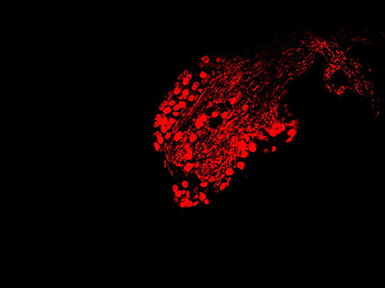

明美显微镜相机MSX11用于免疫荧光切片的成像

免疫荧光法是将免疫学方法(抗原抗体特异结合)与荧光标记技术结合起来研究特异蛋白抗原在细胞内分布的方法。由于荧光素所发的荧光可在荧光显微镜下检出,从而可对于抗原进行细胞定位。借助显微镜相机,从而对显微镜观察到的荧光样品进行成像,还可以保存,并且进行传送。

明美显微镜相机MSX11,是一款采用4/3英寸大靶面的高性能成像芯片,具有2100万高分辨率的高灵敏度相机。通过硬件ISP图像处理芯片的加持,它可以还原样品的细致结构和真实色彩,大大提升了相机运行速度,是荧光拍摄、病理诊断、金相分析和体视观察等应用领域的理想工具。除了搭配我司荧光显微镜,还可以匹配奥林巴斯、徕卡、蔡司、尼康等品牌的显微镜。